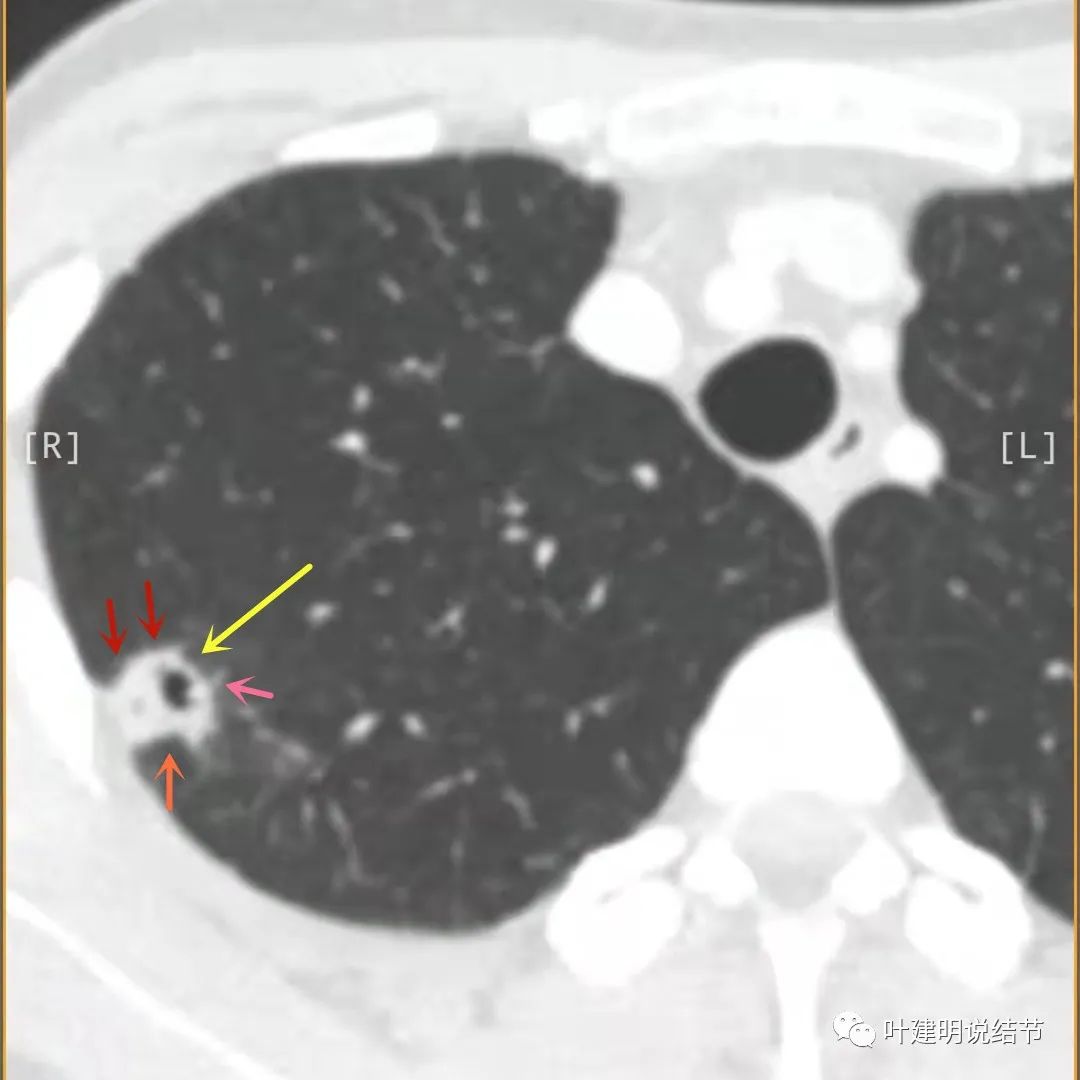

主病灶此层面似三角形,邻近胸膜增厚(蓝色箭头),结节实性部分密度较高(粉色箭头),边缘显模糊(砖色箭头)

上图与恶性较为符合,空洞性病灶,壁厚薄不均,增厚部分还凹凸不平(细红色箭头所指)

上图磨玻璃部分密度过低,且与正常肺组织界限模糊(砖色箭头),粉色箭头示囊壁密度过高的点状,蓝色箭头示邻近胸膜处的增厚